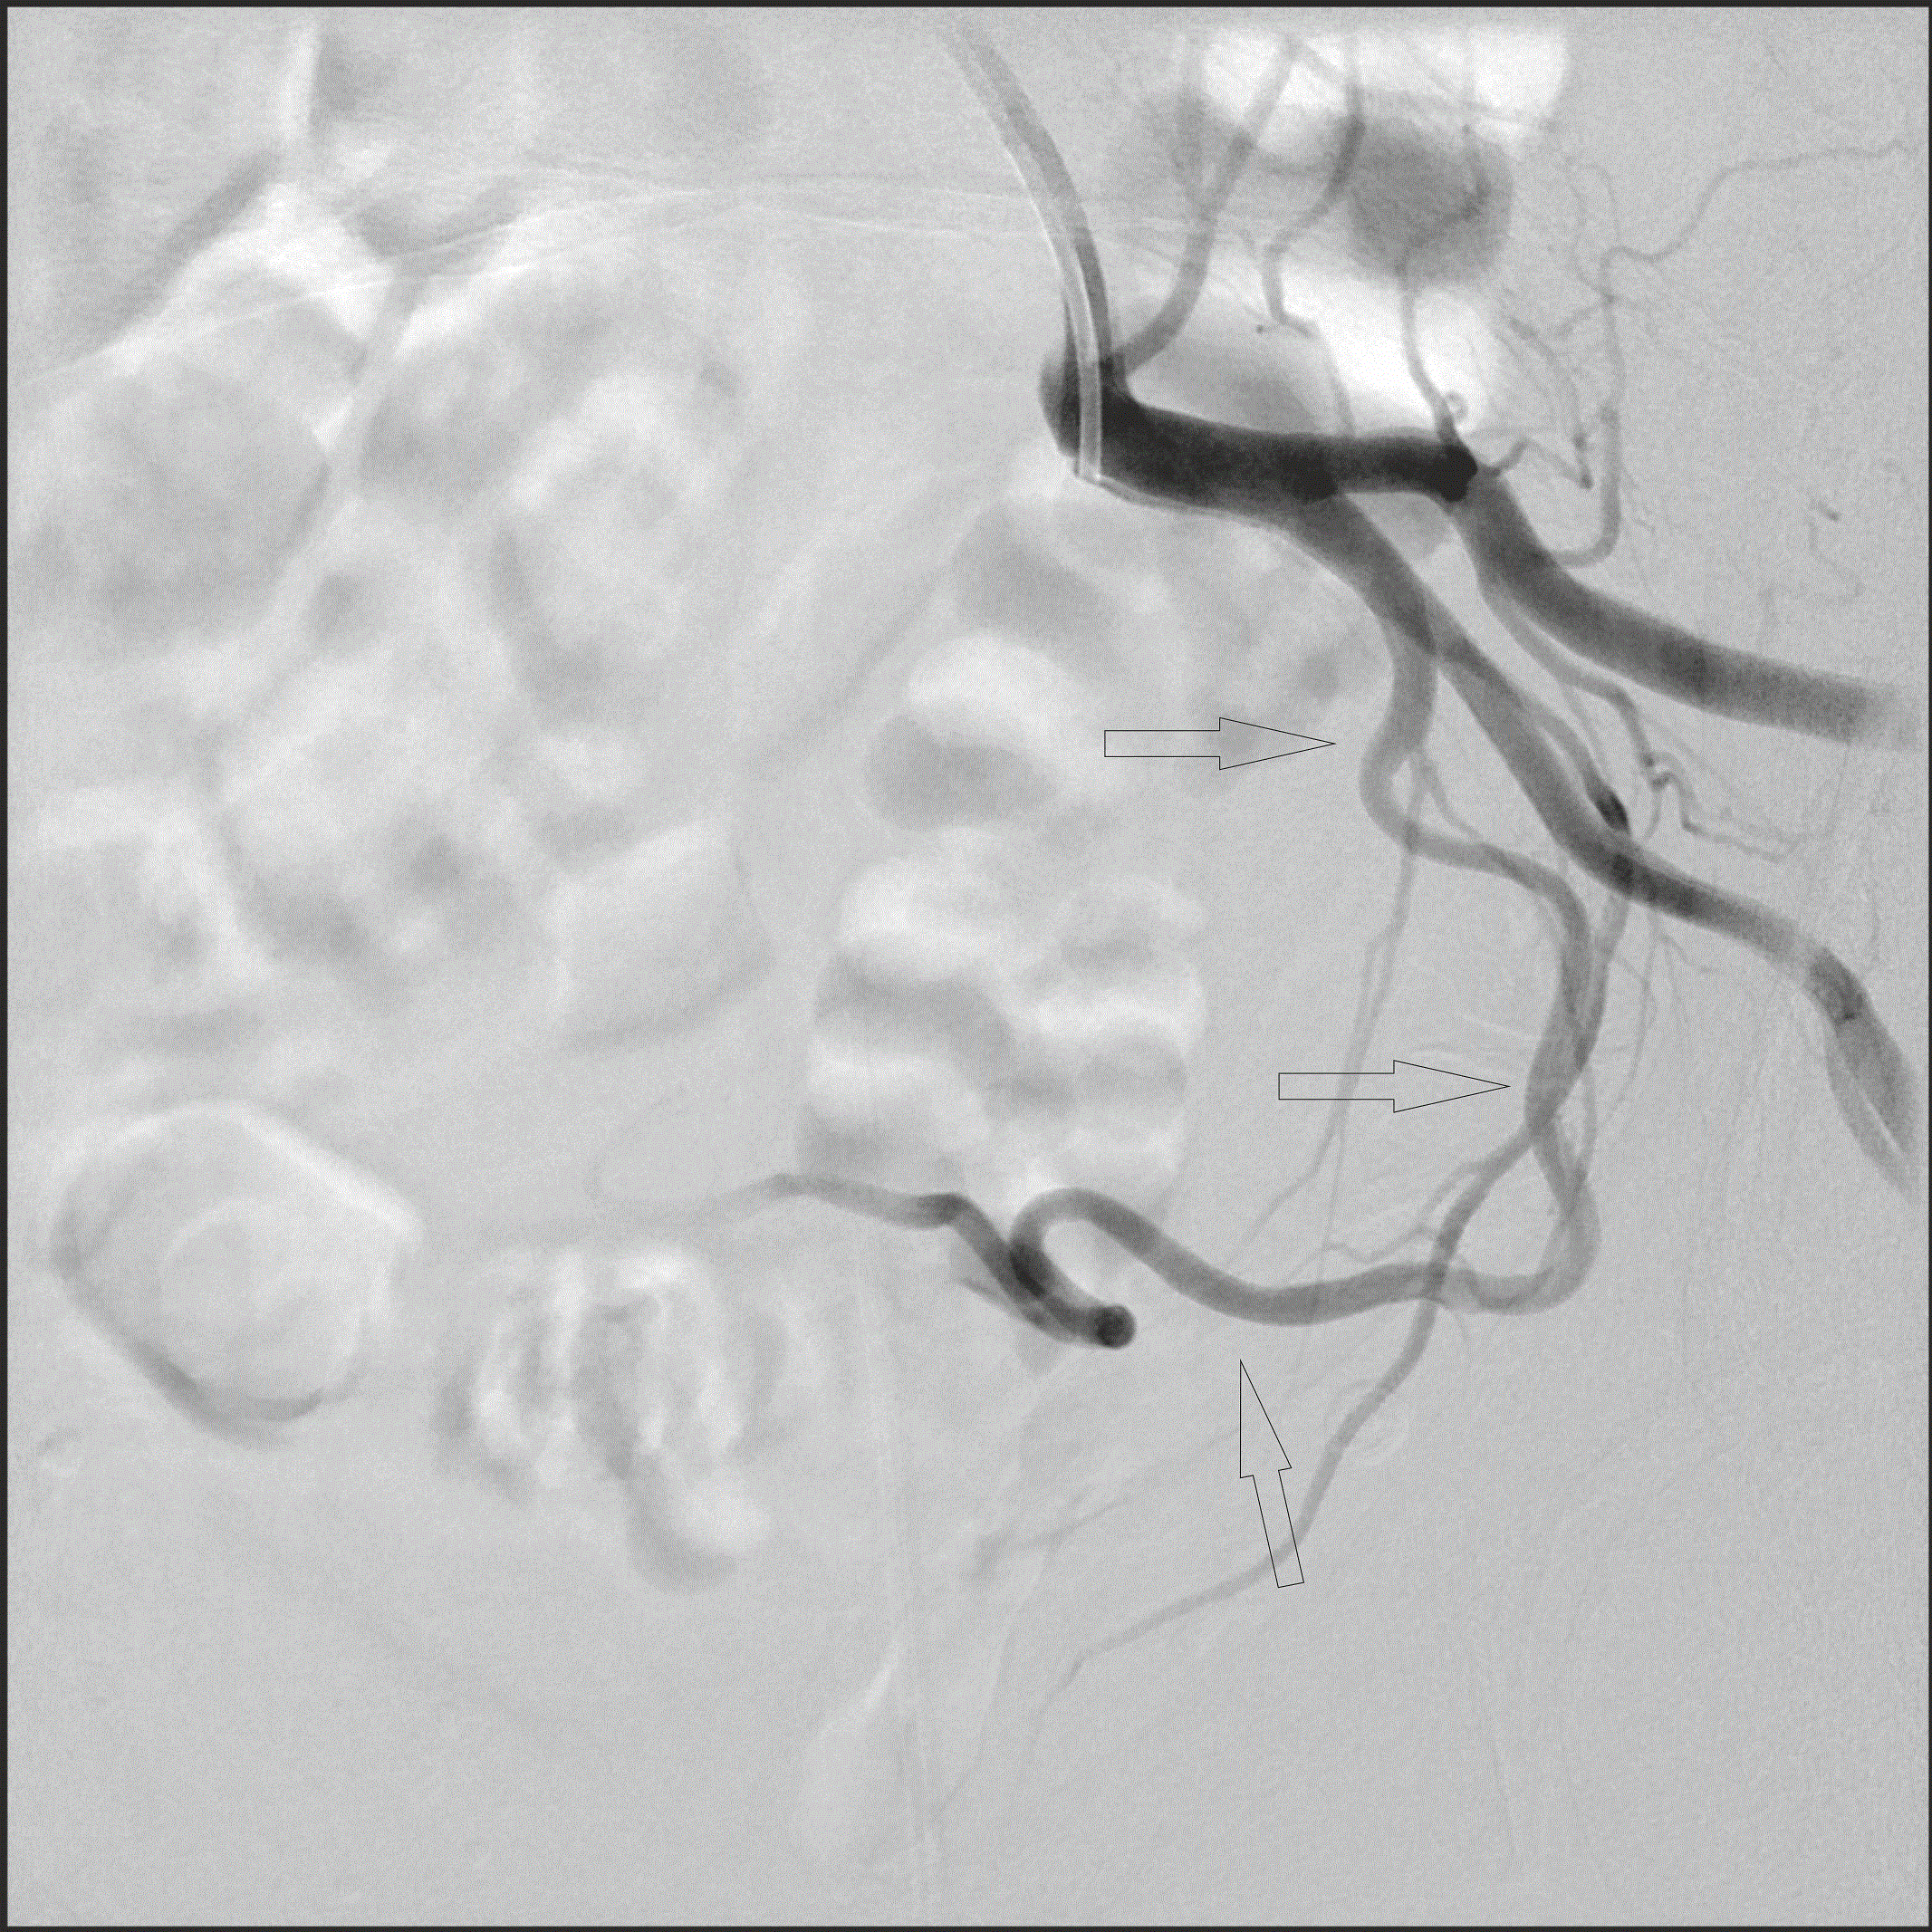

A képeken egy mióma ultrahangos felvétele, valamint mindkét oldali méhverőér érfestéses vizsgálata látható a mióma embolizációja előtt és után.